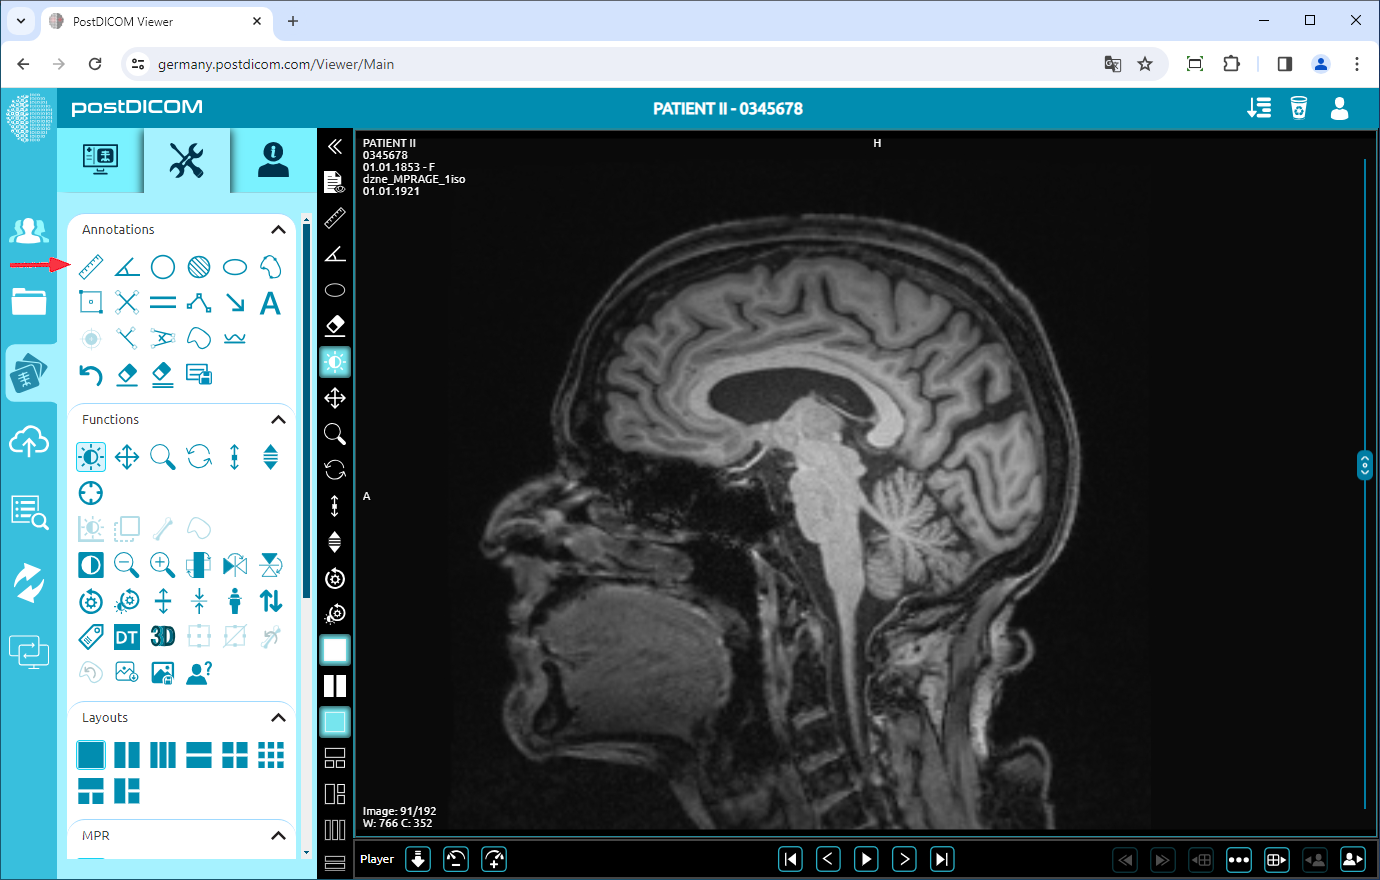

After you have clicked, the tools section will be displayed. In the “Annotations” field, click on the “Ruler” icon on the upper left side of the section.

When you click on the icon, it will turn into blue color and a ruler sign will be shown at the bottom of your mouse pointer. Click on the starting point of the distance you want to measure and move your mouse to the endpoint. Until you click, the distance will appear in blue. Click on the endpoint of the distance and then it will turn into yellow. You will see the distance value next to the end point which is the actual value of the measured distance.